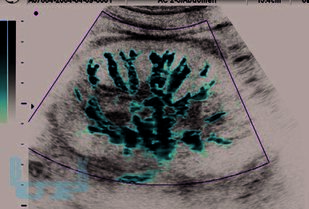

В основу монографии положены результаты собственных исследований и практический опыт авторов, использования ультразвуковых методов исследования мочевыделительной системы у тяжелой группы пациентов в промежуточном и позднем периодах позвоночно-спинальной травмы, проанализированы литературные данные отечественных и зарубежных авторов.

В монографии представлены современные методы комплексного ультразвукового исследования и патологические изменения мочевыделительной системы при позвоночно-спинальной травме. Описаны ультразвуковые симптомы поражения почек и верхних мочевых путей. Представлена разработанная авторами, эхосемиотика нейрогенного мочевого пузыря и эхосемиотика предстательной железы при позвоночно-спинальной травме. Описана технология проведения ультразвукового исследования у прикованных к постели и коляске, нуждающихся в постоянном постороннем уходе больных с последствиями позвоночно-спинальной травмы. Динамическое комплексное ультразвуковое исследование мочевыделительной системы позволяет осуществлять диагностику, мониторинг лечения и оценивать своевременность и эффективность урологического пособия пациентам, перенесшим позвоночно-спинальную травму.